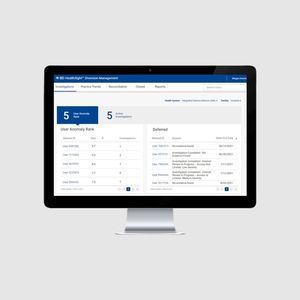

software de gestión de la medicaciónHealthSight™

... BD HealthSight™ Diversion Management es una aplicación de software alojada que utiliza análisis avanzados impulsados por el aprendizaje automático. Basado en una variedad de señales, el software compara el comportamiento ...